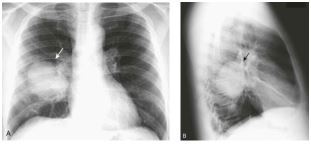

Q

image modality, view, body depicted, abnormality

A

PA and Lateral chest xray, large perihilar mass in right lower lobe